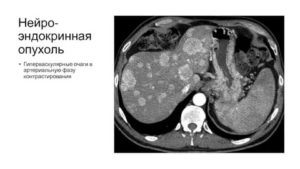

Гиперваскулярное образование

Противоположностью гиподенсивным образованиям являются гиперденсивные ткани. Плотность элемента намного выше остальных участков печени. При проведении томографии подобные образования выглядят более светлыми.

Гиперваскулярный очаг в печени связывают с формированием доброкачественных или злокачественных опухолей. Патологическое состояние характерно для метастазирования из внутренних органов, расположенных рядом: кишечник, молочные железы, легкие, половые органы, грудная клетка.

- МРТ или магнитно-резонансная томография помогает обнаружить внутрипеченочные отсевы развивающейся опухоли и ее дальнейшее распространение на ворота печени. Также этот метод позволяет выявить гиперваскулярное образование печени (узловые гиперплазии, гемангиомы, аденомы, разрывы).

Гиперваскулярные очаги в печени указывают на развитие патологического процесса в организме, поэтому требуют дополнительной диагностики. Назначение лечебной терапии проводится после консультации с онкологом, гастроэнтерологом или гепатологом.

Гиперваскулярное патологическое состояние характеризуется изменением структуры тканей печени с существенным уплотнением в некоторых участках органа. Очаг хорошо заметен на рентгеновском снимке, так как отличается усиленным отражением лучей и повышенной эхоплотностью. Диагностируется как белое вкрапление в структуре печени.

Для измененных тканей характерно скапливание жидкости из-за развитой сосудистой сетки.